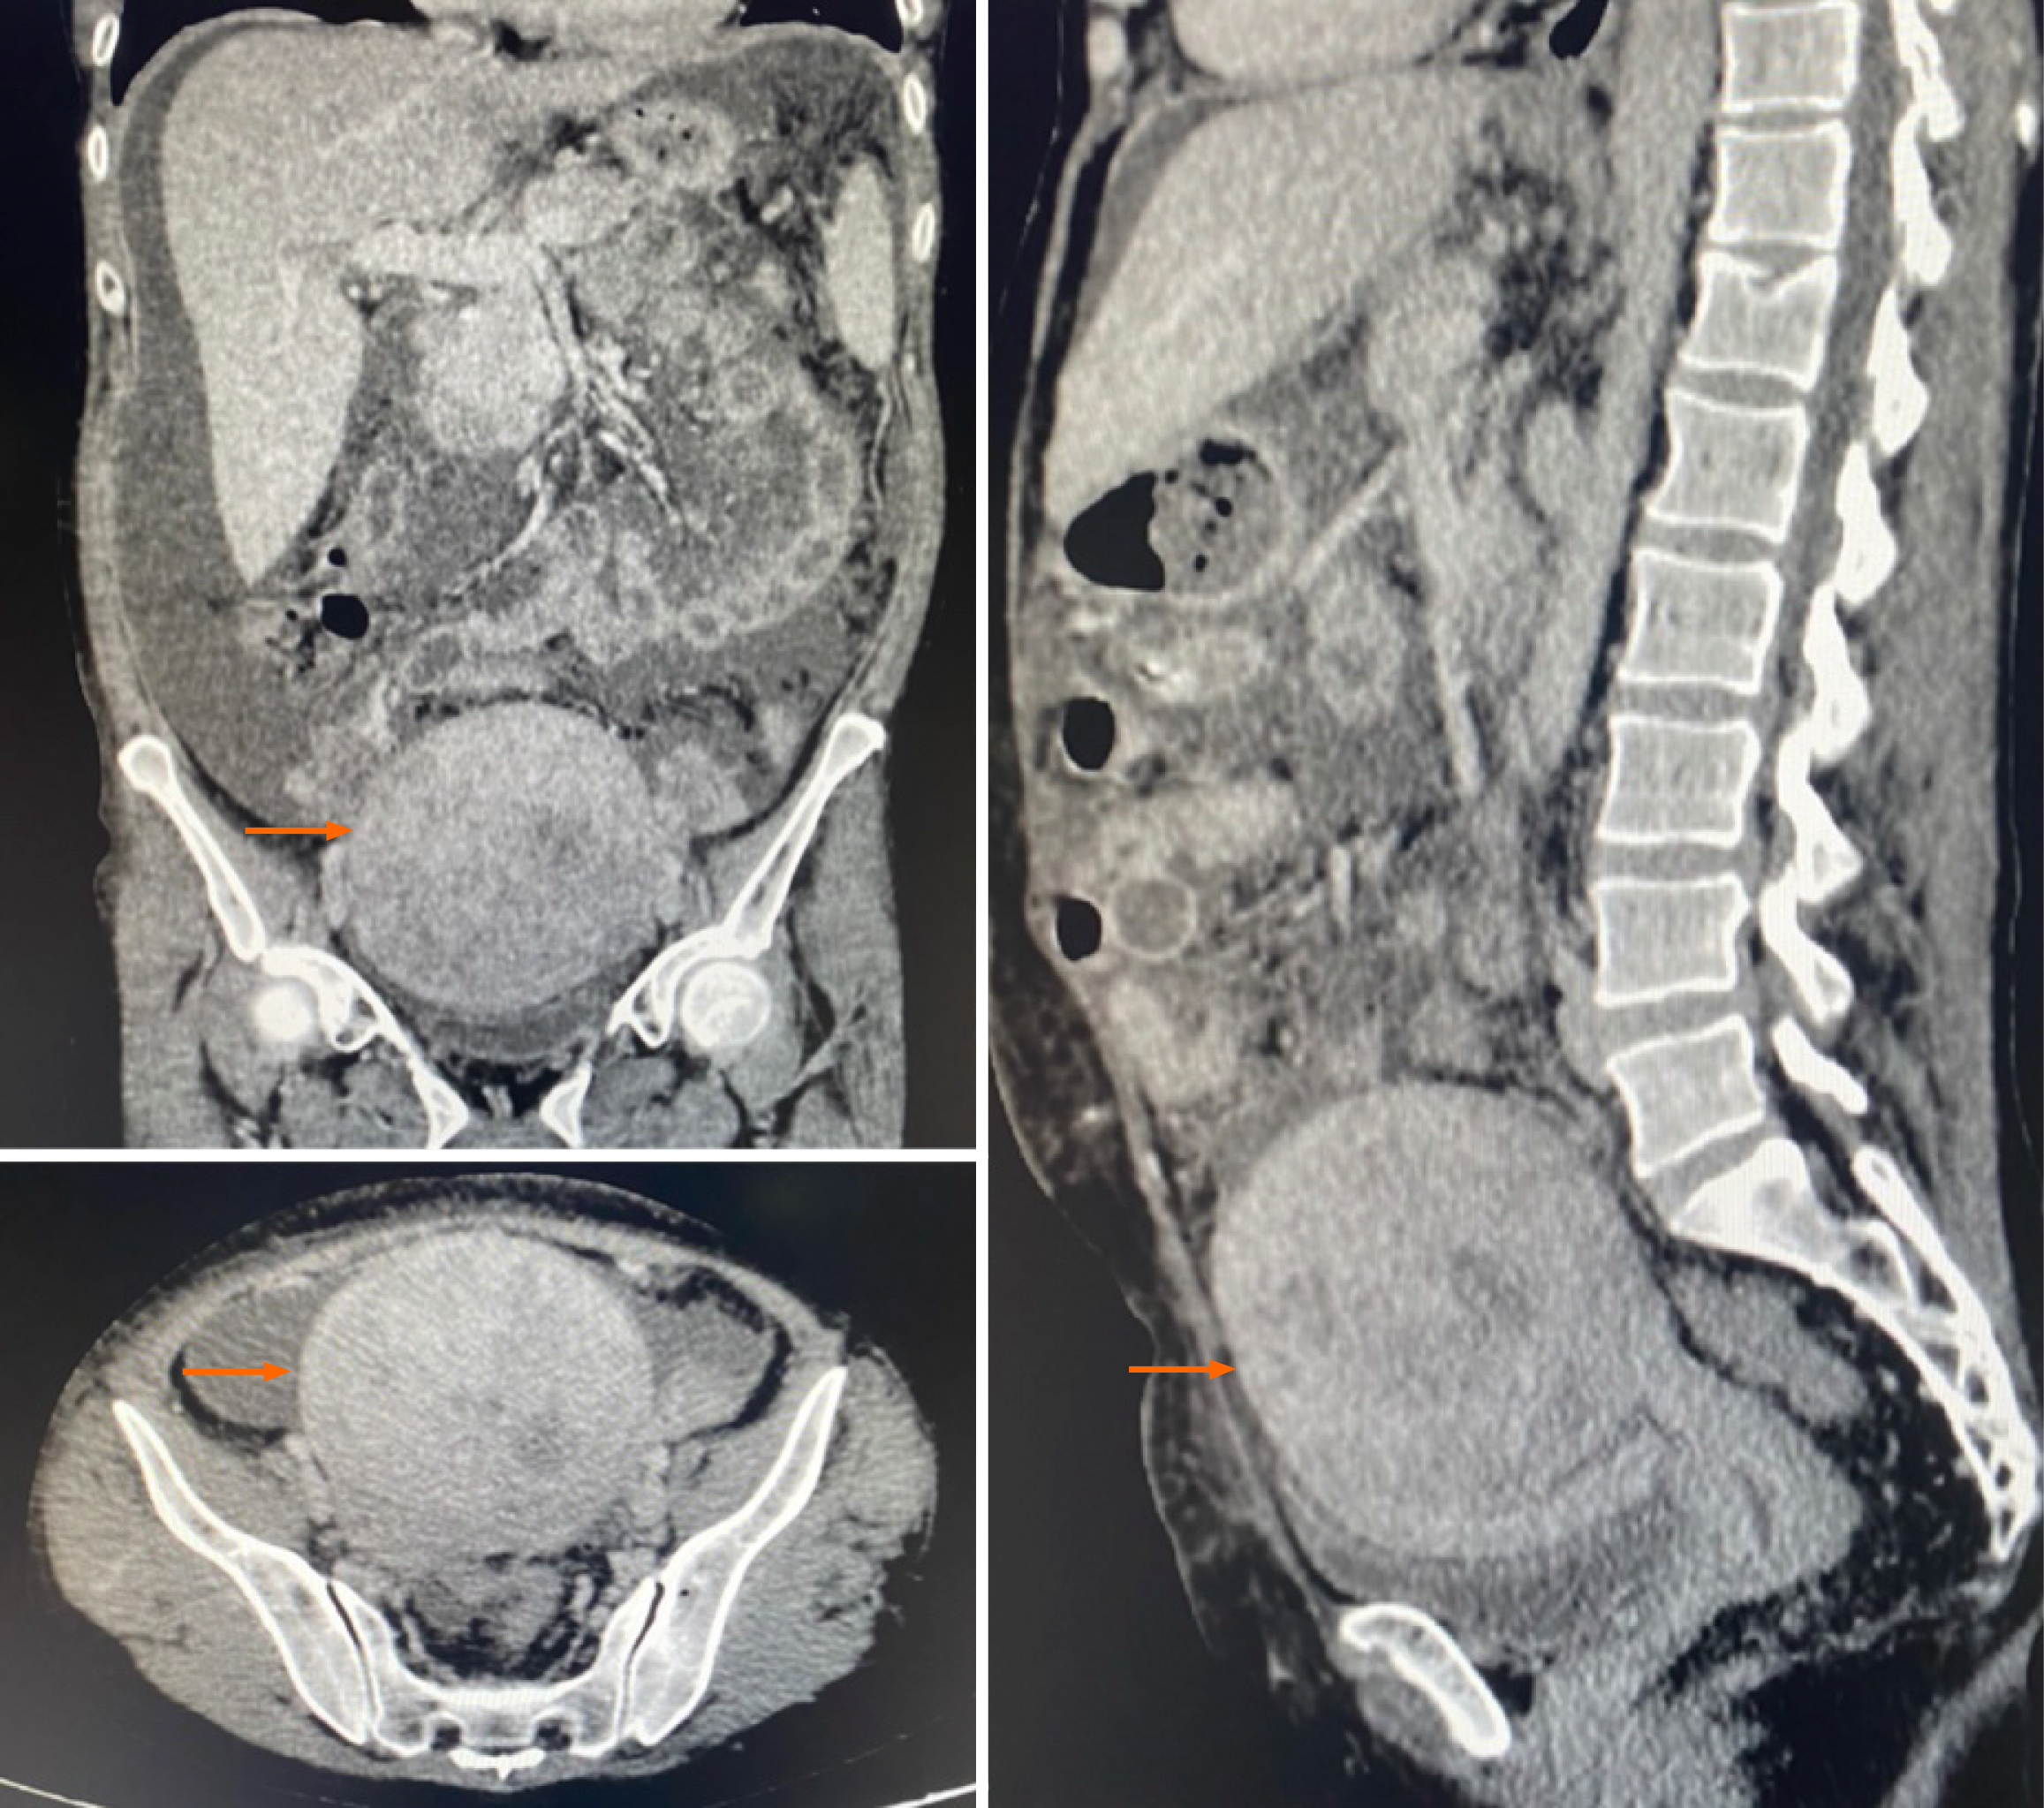

Figure 1 Computed tomography of the abdomen and pelvis showing a well-defined, heterogeneous nodular lesion located in the posterior wall/fundus of the uterus, measuring 10.

4 cm × 10.1 cm × 9.4 cm, associated with moderate ascites (orange arrow).